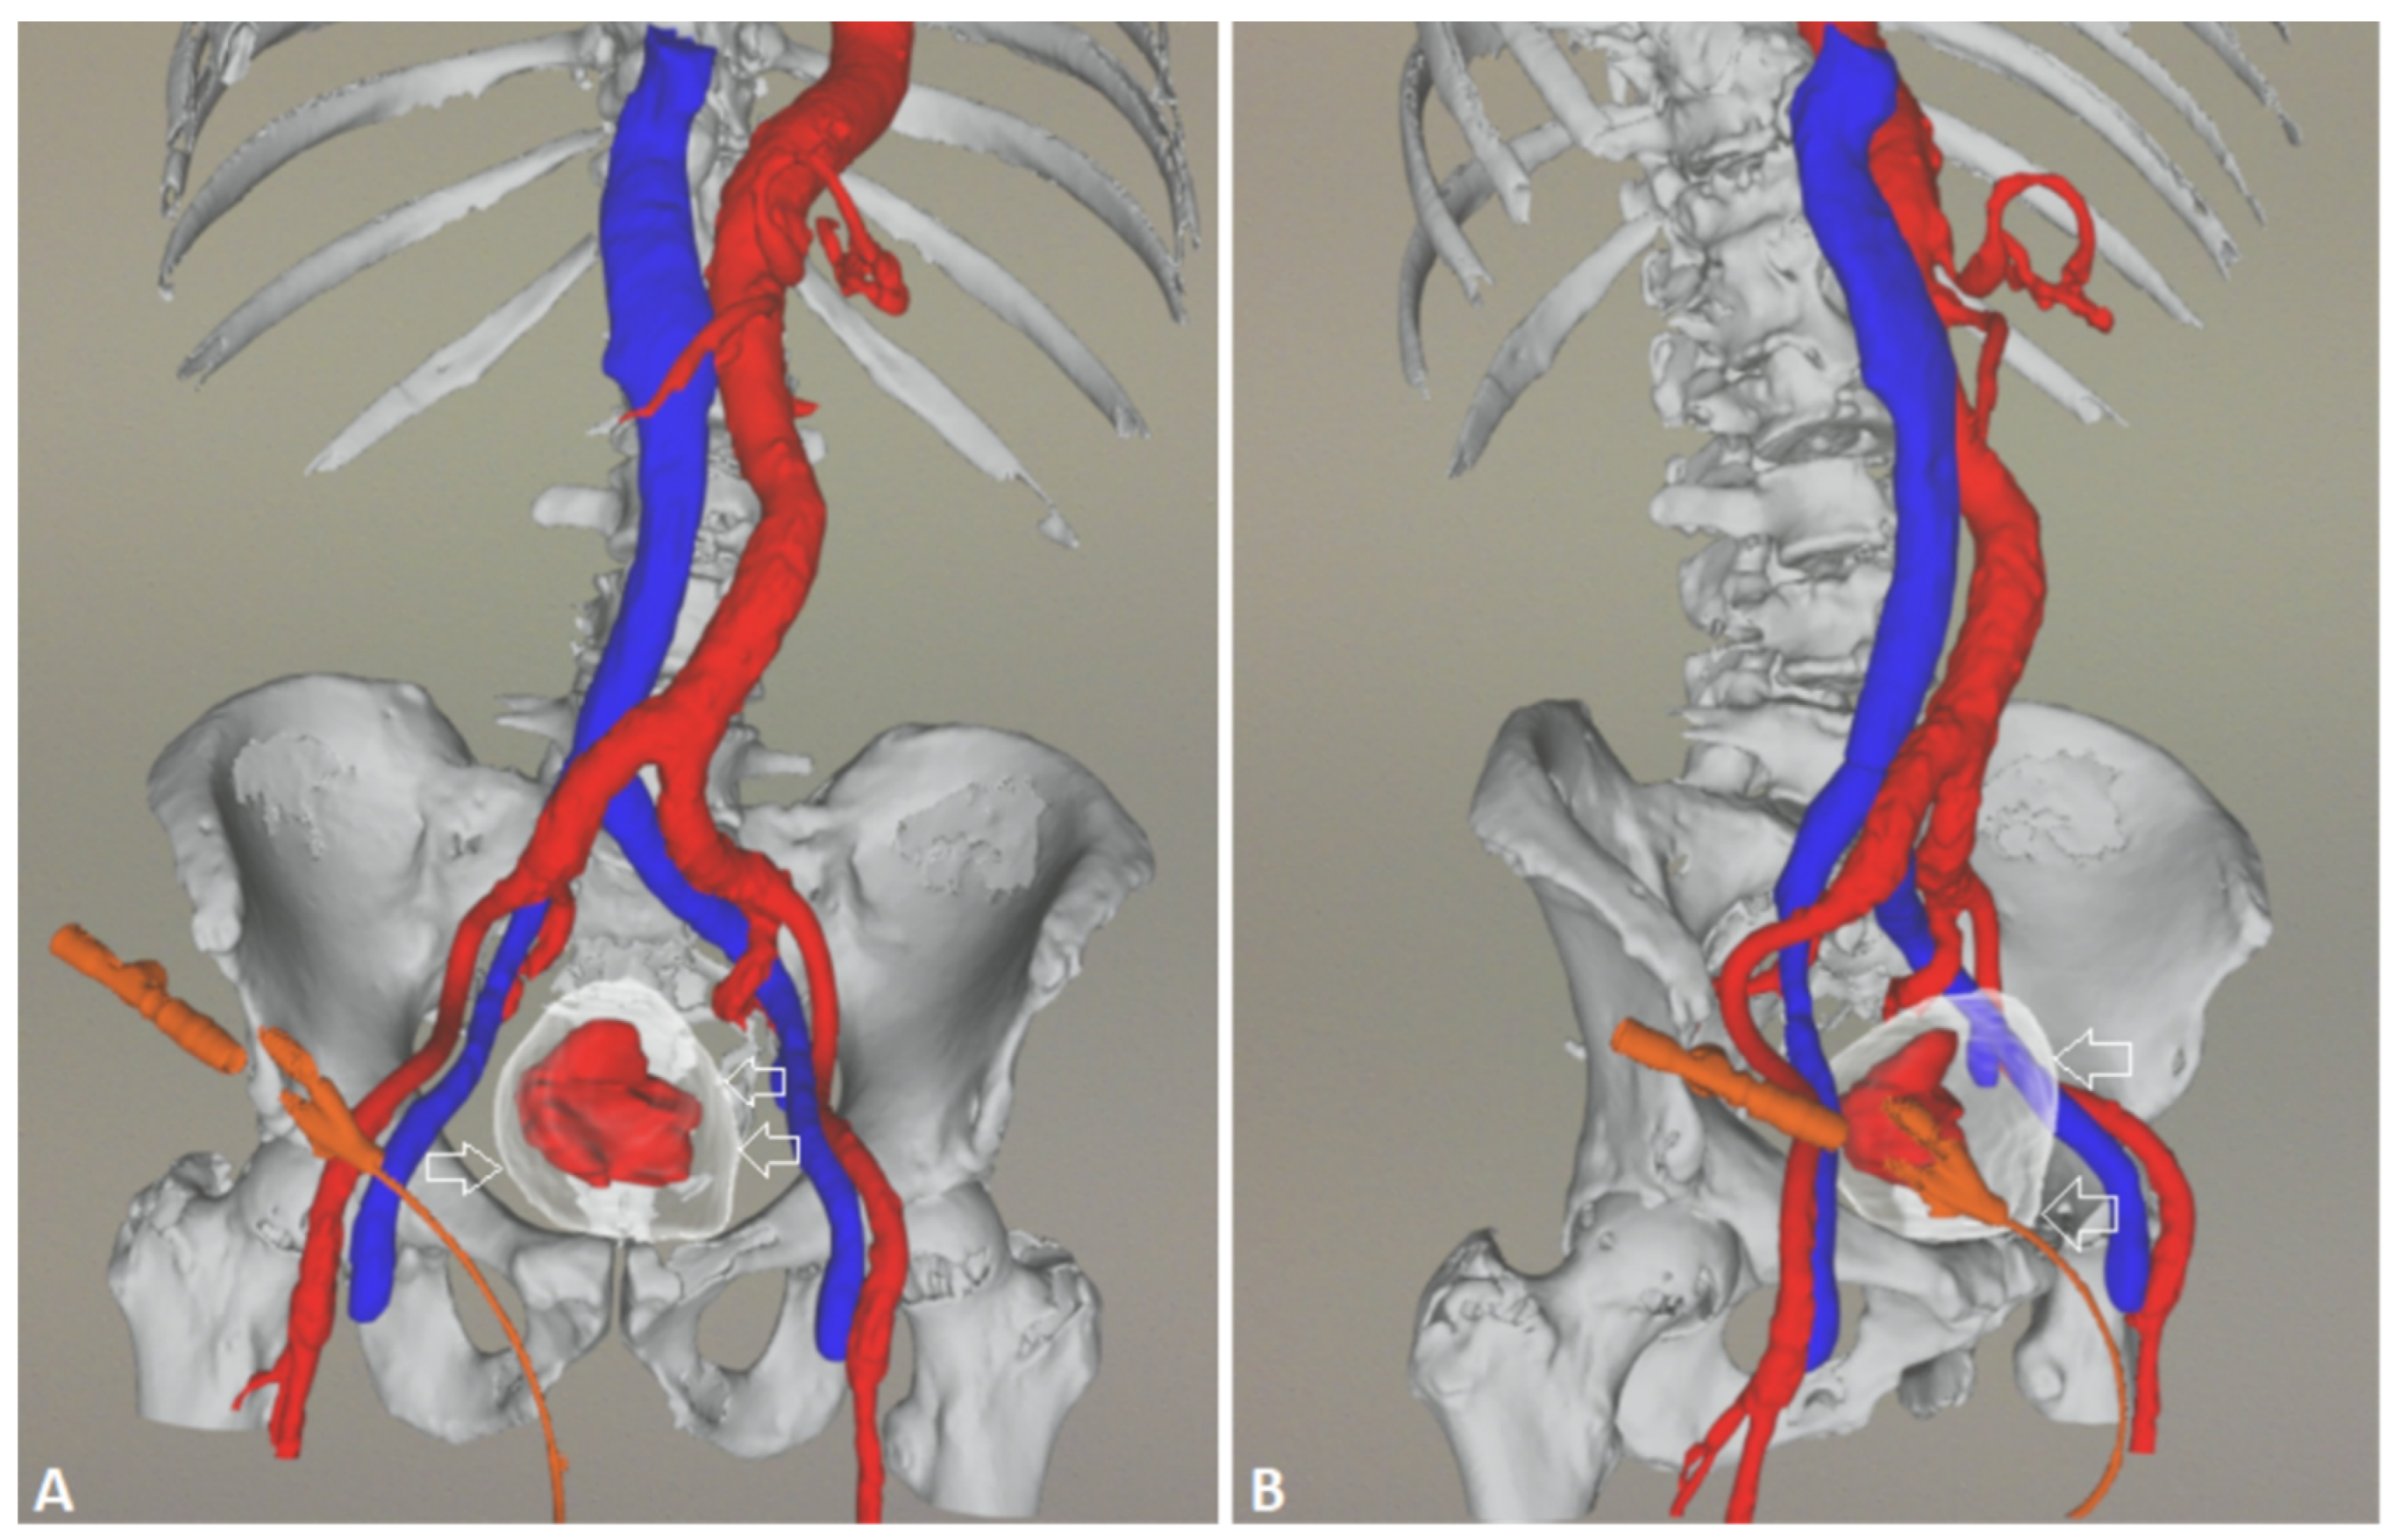

5. A Suggested Algorithm and a Demonstrative Case Report

Technical Details of PAE